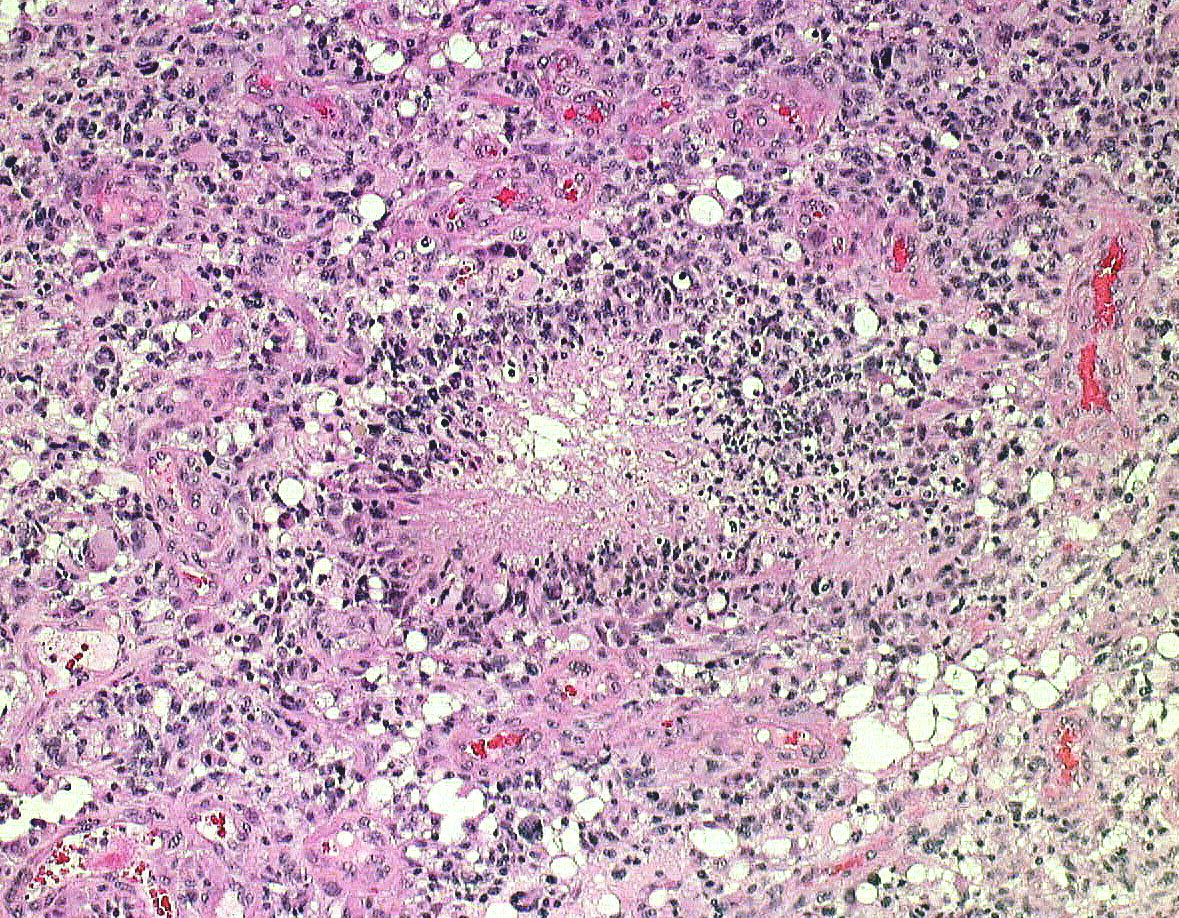

HE染色では細胞核の周りが抜けるような典型的なhalo(左側の写真)があります。1p/19q欠失があり,MIB染色率(右側)は4%でした。

一部で,細胞密度が高く,核の腫大とクロマチンの増量,核間距離の短縮があり,核分裂像が認められ,MIB-1染色率が10%です。組織学的には退形成性乏突起膠腫グレード3とされました。

同じ患者さんからの2カ所の病理標本です。左は乏突起膠腫グレード2と診断できますし,右は退形成性星細胞腫グレード3と診断できます。光顕診断では,両方合わせて,退形成性乏突起星細胞腫グレード3となります。ちなみに,olig2 強陽性,MIB-1 9%,1p/19q codeletionがありました。遺伝子診断を加えると退形成性乏突起膠腫となります。乏突起膠細胞系腫瘍では,術中迅速病理診断や定位脳生検術での診断は誤診を招くことが多くて危険です。

左側の病理像はanaplastic oligodendroglioma AO あるいはoligodendroglioma ODです。しかし,右の画像の様にpseudopallisading (necrosis)を示す部分があり,WHO grade 4と診断したくなるのですが,oligodendrglioma grade 3 ではnecrosisが混在してもgrade 3としてよいのです。